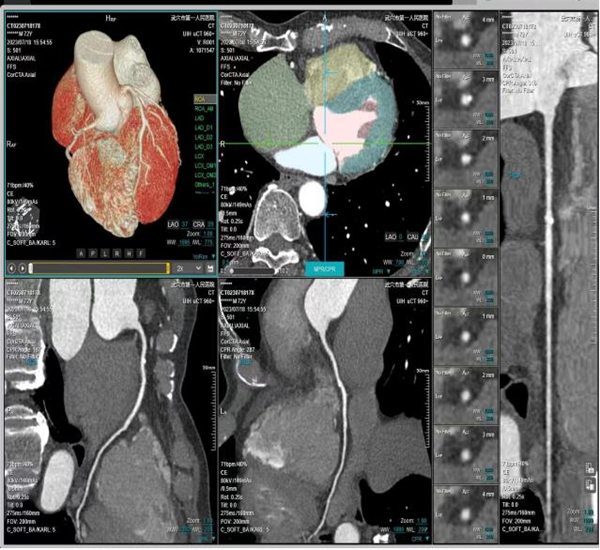

全身多部位大血管联合成像 注射一次造影剂即可

一次对比剂注射及CT扫描,即可获得多系统、多部位平扫、动静脉造影和灌注图像,如“4D全脑一站式”成像、胸痛三联、冠脉CTA+头颈部CTA等。

“一站式”检查,避免多次对比剂注射和分次检查,不但减少了射线辐射,也降低了反复使用对比剂诱发肾功能损害的风险,同时也满足临床对于疑难危重病例的快速诊断的需求。一次扫描可了解全身动脉血管的病变情况,特别适合健康人群中的高端体检。